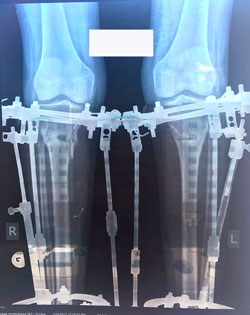

Исходник - 19 лет.

Дата операции 25.05.2017г.

В процессе круток

58 дней.

Через 2 недели можно на снятие аппаратов.

Дата снятия аппаратов 10.08.2017г.

Срок лечения 75 дней.